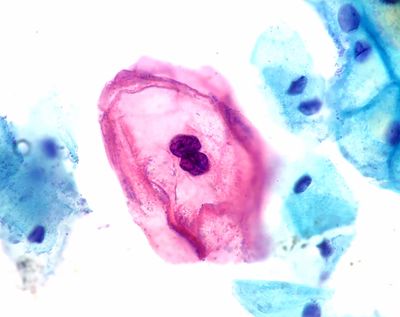

Almost all cervical cancers are caused by HPV infections, most often by two strains which all versions of the HPV vaccine provide excellent protection against. As smoking rates have declined, HPV has also become the cause of more than half of the US’s oropharyngeal (throat) cancers.